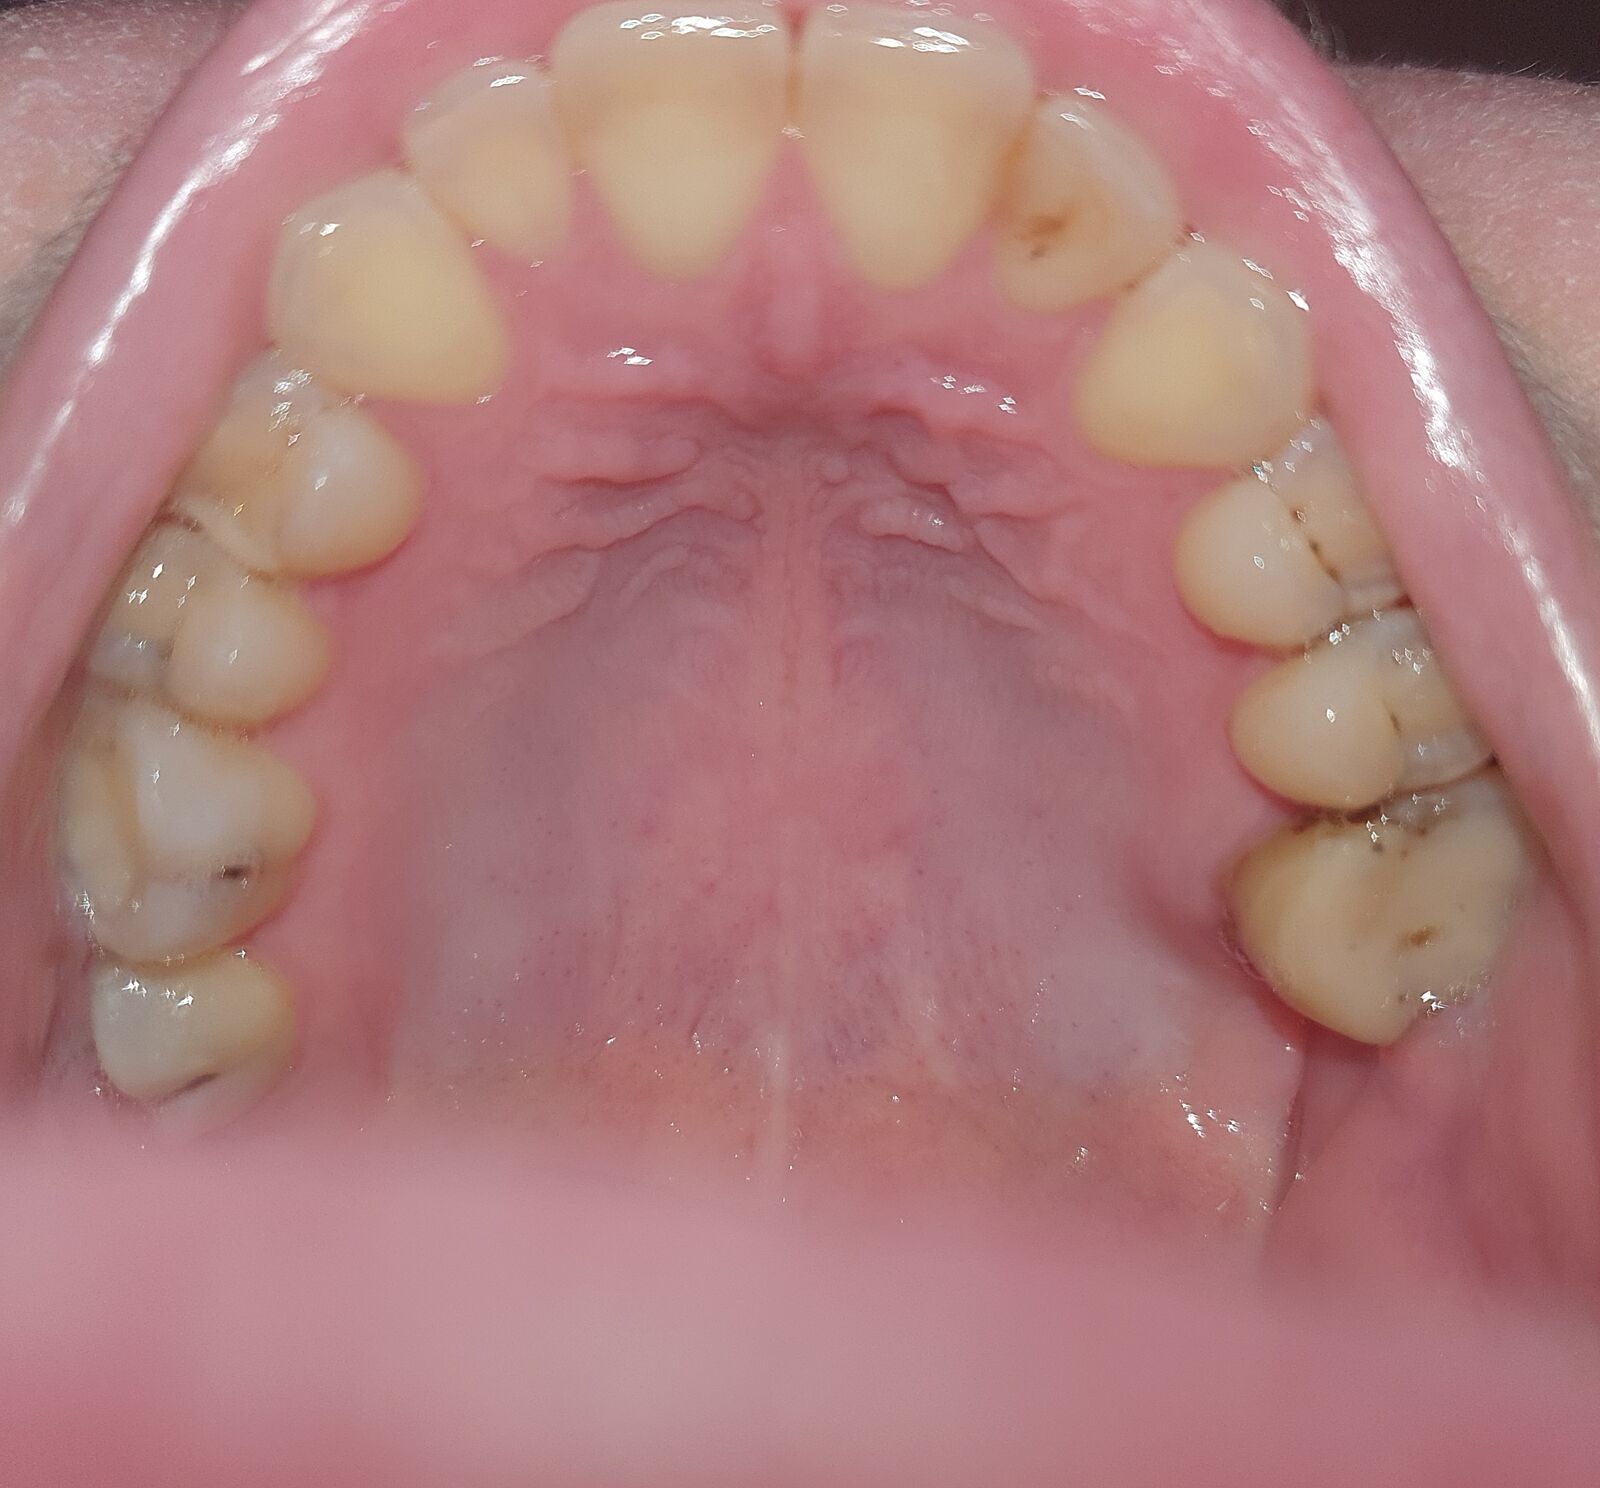

Зубам капец?((( Впечатлительным не смотреть

Так вышло, что было очень много проблем и очень-очень много финансов уходило за последние года 4...прямо ОЧЕНЬ много..зубы не лечила и снаружи катастрофы не было сильно заметно,но вот заколол верхний зуб, решила изнутри сфотографировать, а там катастрофа..все в кариесе, все в трешинах ((((((( ужас...неужели если нет денег на виниры, то зубам теперь капец в таком состоянии?

Это вы капецовых ситуаций не видели. У вас все не та плохо, как вам кажется. Идите и начинайте лечение.

2

причем тут виниры?все вовремя нужно делать,а теперь да готовте бабло и много

Да нет,все пломбируется ничегг критичного

Ну не совсем уж капец, подлечите, хорошо почистите у стоматолога и норм будет.

Начинать нужно с пломб, зачем виниры? Тем более, Вы сами сказали, что эстетически все нормально. Пломбируйте по 1 в месяц, можно ужаться, не так уж много это по деньгам.

Нормальные зубы. Это далеко не капец

Пломбы и коронки на моляры. Там большие полости, и если не лечить коронкой, то будет ненадежно

Не без кариеса, но вот этот черный налет - еще не беда, одна дырочка точно есть.